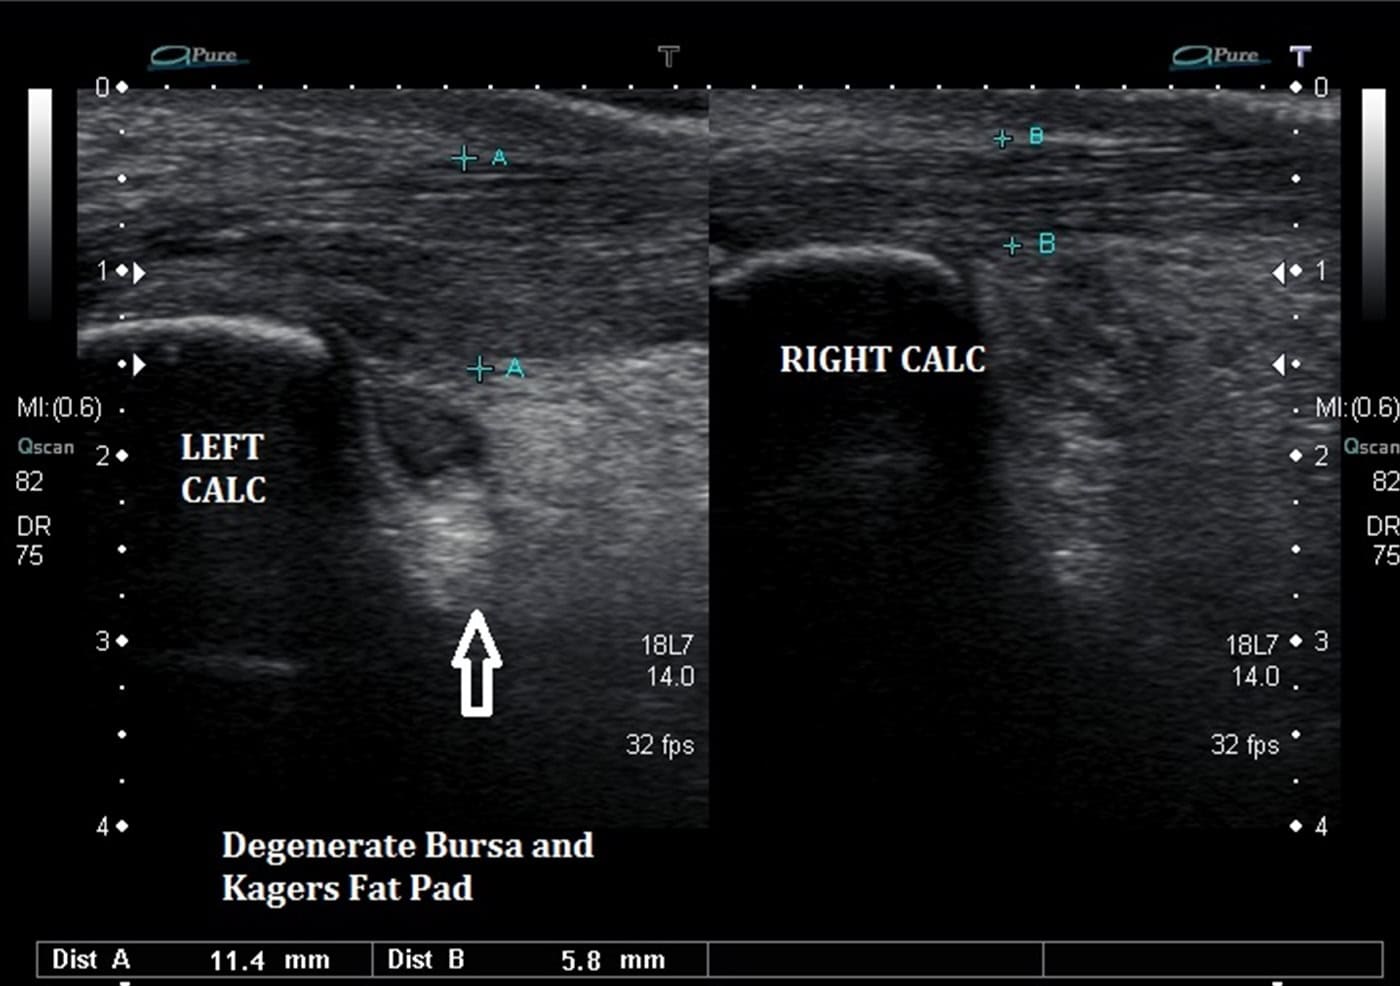

Kager's Fat Pad Irritation Ankle, Foot and Orthotic Centre Can Certain Pads Cause Irritation Pad rashes are common among menstruating women around the world. The continuous rubbing of the pad against the skin can cause chafing. Sometimes the rash can be the result of irritation from something the pad is made from. Sanitary pads often contain fragrances, synthetic materials and chemicals that can irritate the sensitive external genital (vulvar) skin in some. While any. Can Certain Pads Cause Irritation.

Kager's Fat Pad Irritation Ankle, Foot and Orthotic Centre Can Certain Pads Cause Irritation Sanitary pads often contain fragrances, synthetic materials and chemicals that can irritate the sensitive external genital (vulvar) skin in some. Chemicals, perfumes, or synthetic materials in pads might trigger allergies. Does your skin get irritated when you wear sanitary pads? The continuous rubbing of the pad against the skin can cause chafing. While any sanitary pad can cause a rash. Can Certain Pads Cause Irritation.